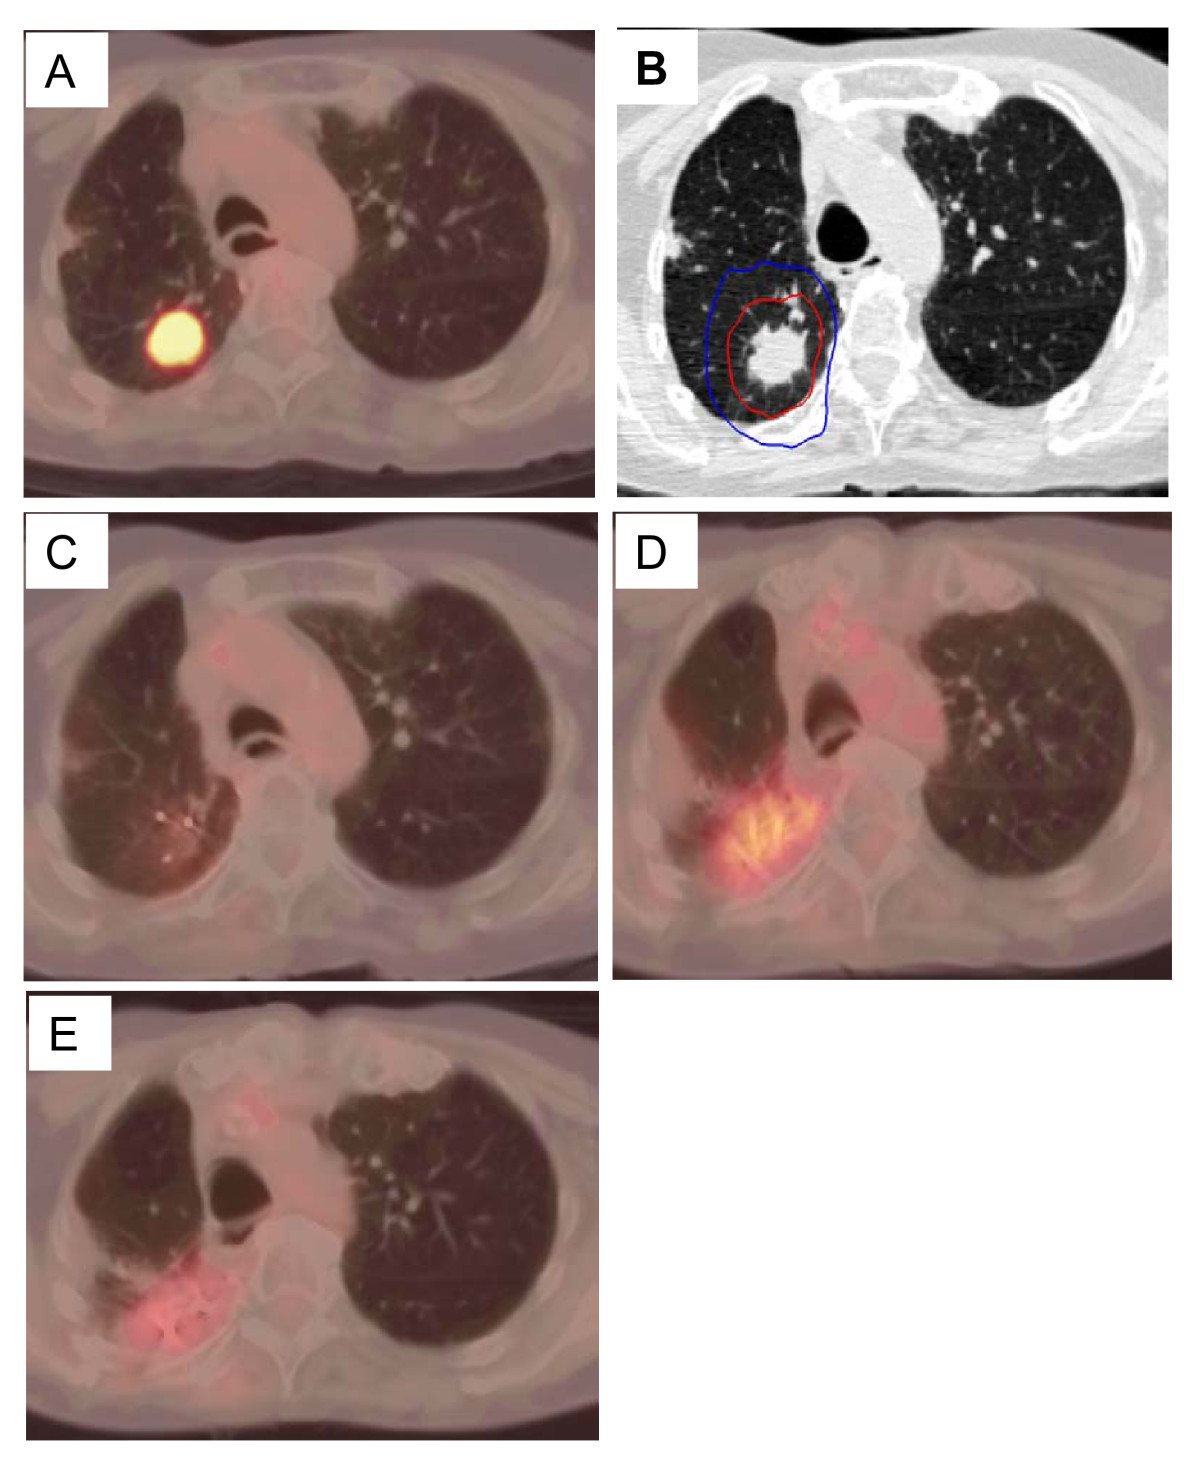

Figure 4. Right upper lobe clinical stage IA NSCLC treatment planning PET/CT with a tumor SUVmax of 10.5 (A), planned radiation dose distribution (B: the planning treatment volume receiving 45 Gy shown in red and the 30 Gy isodose line in blue), and PET/CT at 6, 12, and 18 months post-treatment (C, D and E) show an initial decrease in tumor SUVmax to 1.5 followed by a transient radiation induced increase (tumor SUVmax = 4.0) which resolves by 18 months (tumor SUVmax = 2.5).

Click image to view larger.